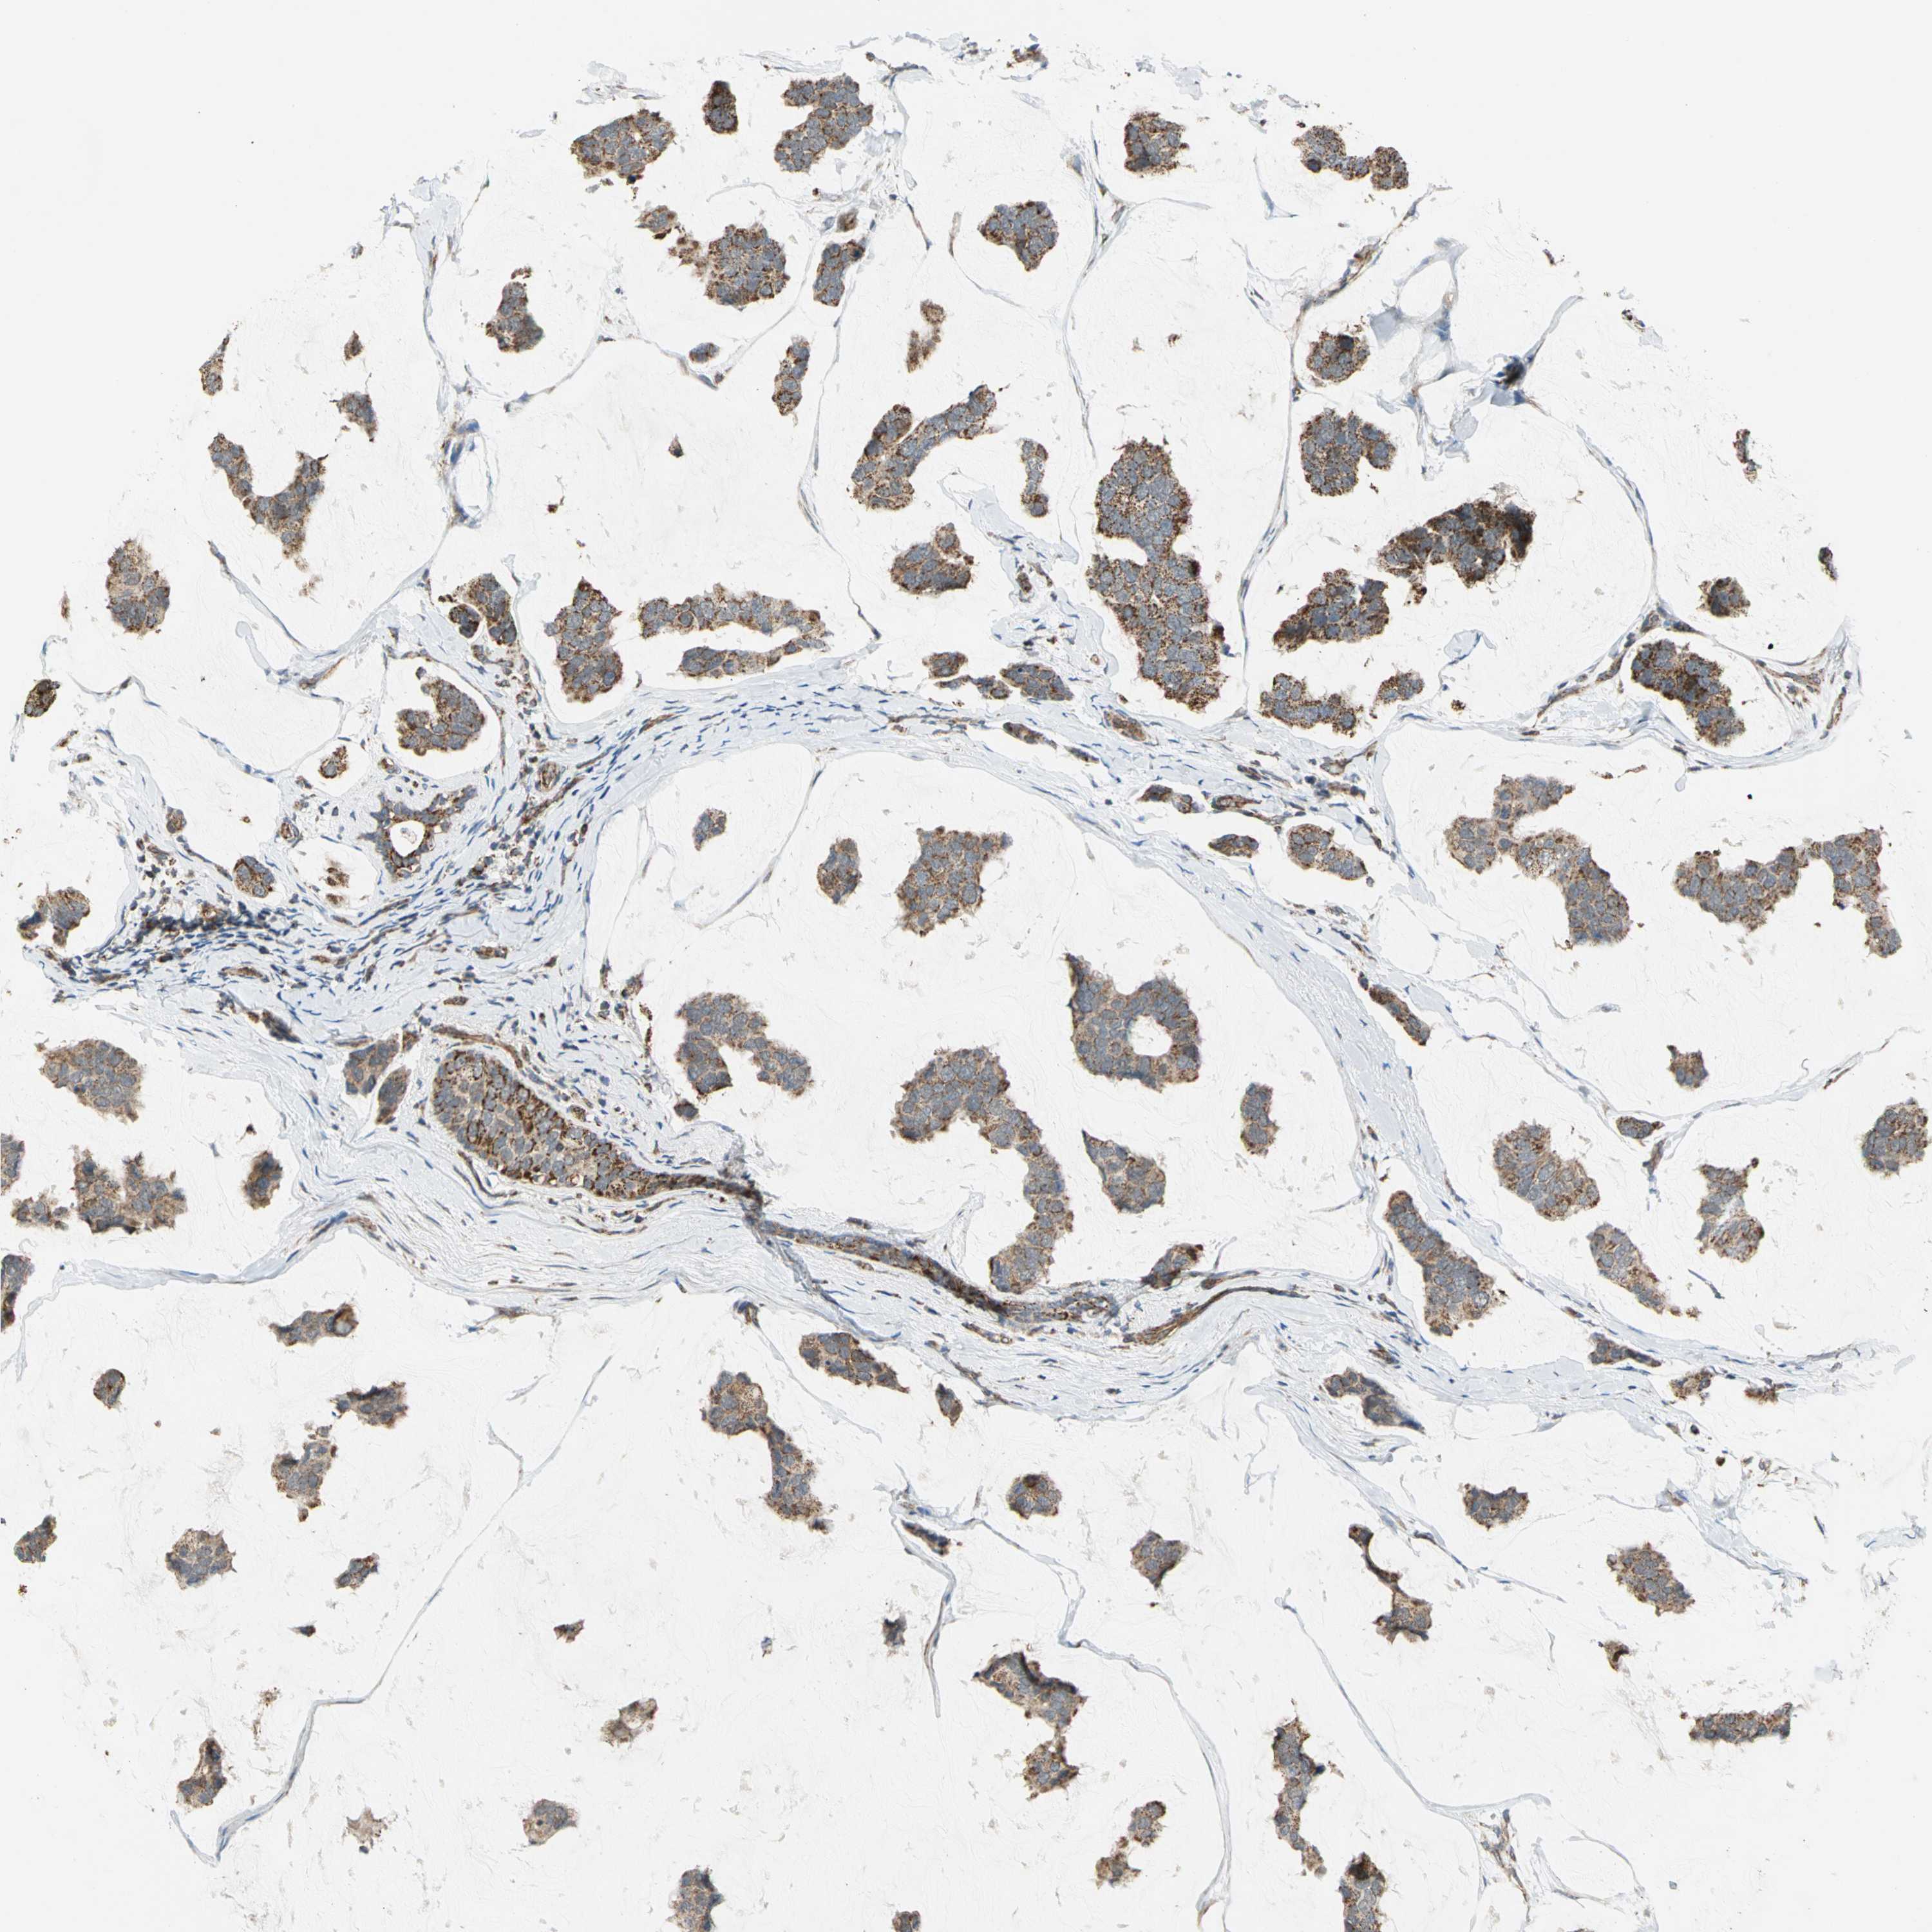

BRCA TCGA BRCA VALIDATION PROTEIN EXPRESSION